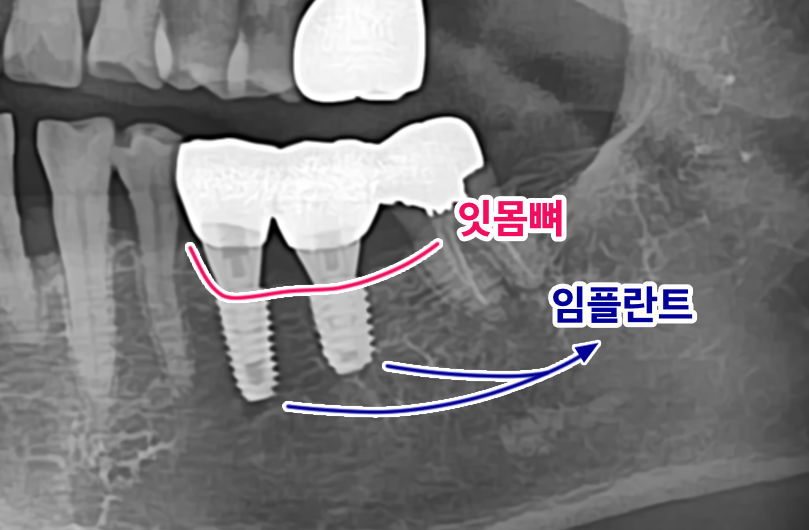

치과에서 심은 임플란트의 상태 확인을 위해서도 사용되며